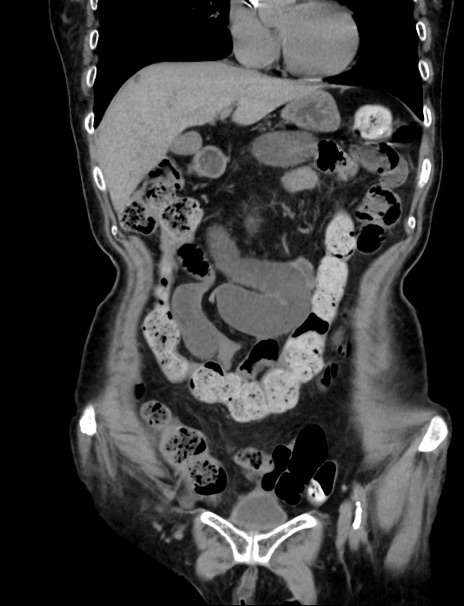

症例33(冠状断像)

【症例】70歳代 女性

【主訴】心窩部痛

【現病歴】延髄病変の精査・加療にて神経内科入院中。本日より心窩部痛あり。

【既往歴】虫垂炎

【身体所見】右下腹部を中心に圧痛と反跳痛あり。

【データ】WBC 10900、CRP 0.02